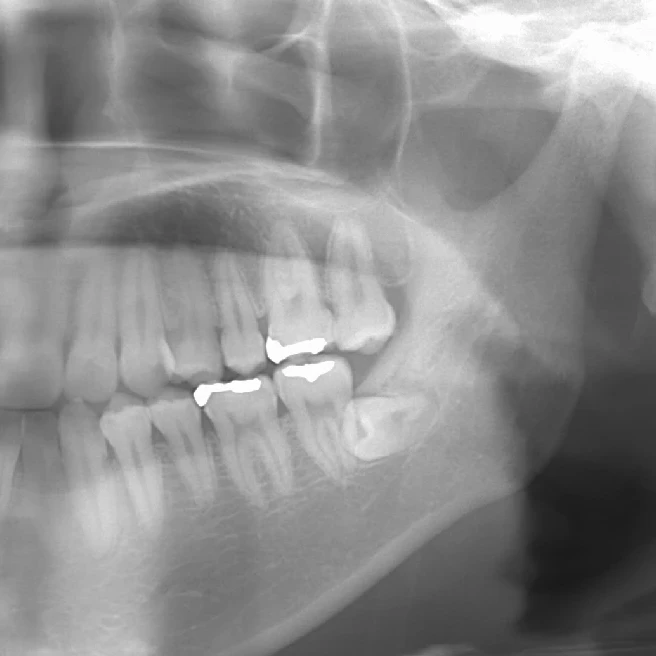

現代人は顎が小さく親知らずがまっすぐ生えることができないため、親不知は多くの場合、横倒しになっていて、骨の中に埋まっています。

埋まっている親不知の周りの骨を削り出し、歯を分割して抜いていくことになります。当然抜歯後は穴が開き、そこに血液がたまり、線維状になり、骨化していくことで治癒します。その肉になる過程で痛み止めを服薬していくことになるのですが、通常の飲むタイプの痛み止めですと胃で分解吸収され、全身にいきわたってしまうため、患部に作用する鎮痛成分は飲む量に比べて非常に僅かな量なのです。